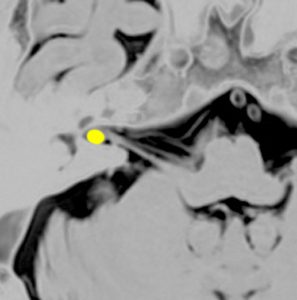

また,この患者さんは急に容態が悪くなって意識障害となりました。何故なら腫瘍の内部で出血したからです(黄色の矢印の部分)。第4脳室が詰まって閉塞性水頭症になって側脳室が拡大しています(右の画像)。

大きなのう胞性聴神経腫瘍です。いくつかの袋が重なって腫瘍を形成しています。橋や延髄(脳幹部)が変形して,第4脳室がつぶれて閉塞しています。袋の周りが白く線状に造影されているのですが,この袋の壁だけに腫瘍細胞がありますから,これを剥がすように摘出します。顔面神経が薄くなって袋の壁にくっついているのですが,袋を破ってくしゃくしゃにすると顔面神経の位置が変わってしまって,顔面神経を損傷することがあるので要注意です。のう胞性聴神経腫瘍の方が顔面神経麻痺の後遺症の頻度が高いという報告もあるくらいです。この患者さんは迷走神経と舌咽神経の圧迫も強くて,ご飯を飲み込むことが難しくなっていました(嚥下障害)。